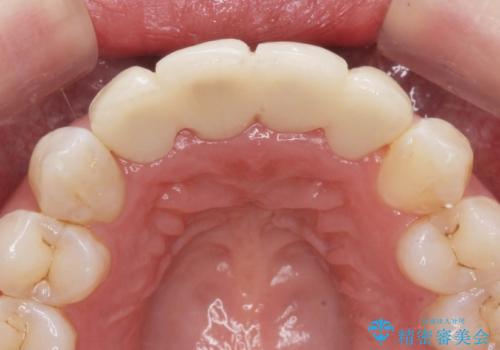

仮歯のまま放置していた前歯をセラミックに

- 仮歯のまま放置してしまい、変色を改善しきれいなセラミッククラウンをいれたい、と希望され来院されました。

特に虫歯の再発や神経の症状等問題を認めなかったので、審美的に優れるセラミッククラウンに仮歯を置き換えていきます。

- 52.8万円(ジルコニアクラウン×4・仮歯×4)費用は治療当時の料金となります